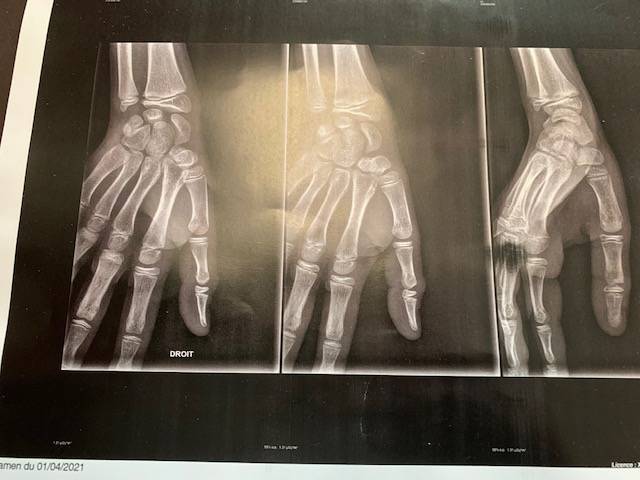

Le patient, un jeune sportif, présentait une fracture de la base de la deuxième phalange (P2) du pouce droit, consécutive à une chute survenue lors d’un entraînement de handball. La lésion a été confirmée par la radiographie apportée le jour du rendez-vous.

Après examen clinique et retrait du bandage temporaire posé en urgence, notre orthopédiste-orthésiste a procédé à la réalisation d’une orthèse thermoformée du pouce sur mesure, directement moulée sur la main du patient.